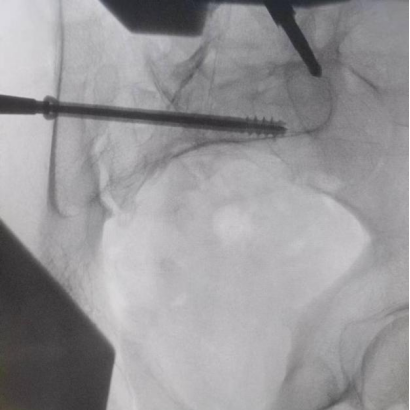

圖為透視下見置入的骶髂螺釘,位置、長(zhǎng)度精準(zhǔn),無絲毫偏差